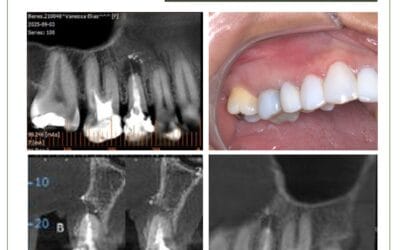

Sinusite odontogênica bilateral. Caso de sinusite com origem odontológica em paciente que passou por diversos tratamentos médicos.

Ao exame clínico, os dentes 16 e 26 não apresentaram vitalidade positiva, sendo que o dente 26 apresentou dor à palpação e percussão. A radiografia panorâmica e a periapical revelaram tratamento endodôntico realizado no dente 27 e não forneceram imagens conclusivas sobre a relação entre sinusite e infecção endodôntica. O exame tomográfico revelou imagens de rompimento de cortical do seio maxilar e espessamento da mucosa sinusal em torno dos ápices.

Diagnóstico: sinusite de origem odontológica ou síndrome endo-antral, bilateral, causada por periodontite apical nos dentes 16 e 27. Os dentes foram tratados endodonticamente e houve remissão dos sintomas.